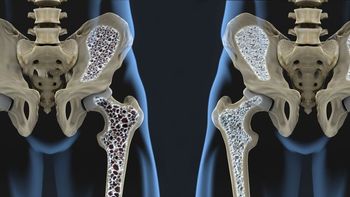

New treatment guidelines for osteoporosis from the Endocrine Society now include romosozumab for postmenopausal women with severe osteoporosis. Learn more in this report.

Bone mineral density was preserved over a three-year period in patients with rheumatoid arthritis treated with biological/targeted synthetic disease-modifying antirheumatic drugs (DMARDS) but declined in those who received only conventional-synthetic DMARDs, say researchers recently writing in Rheumatology.